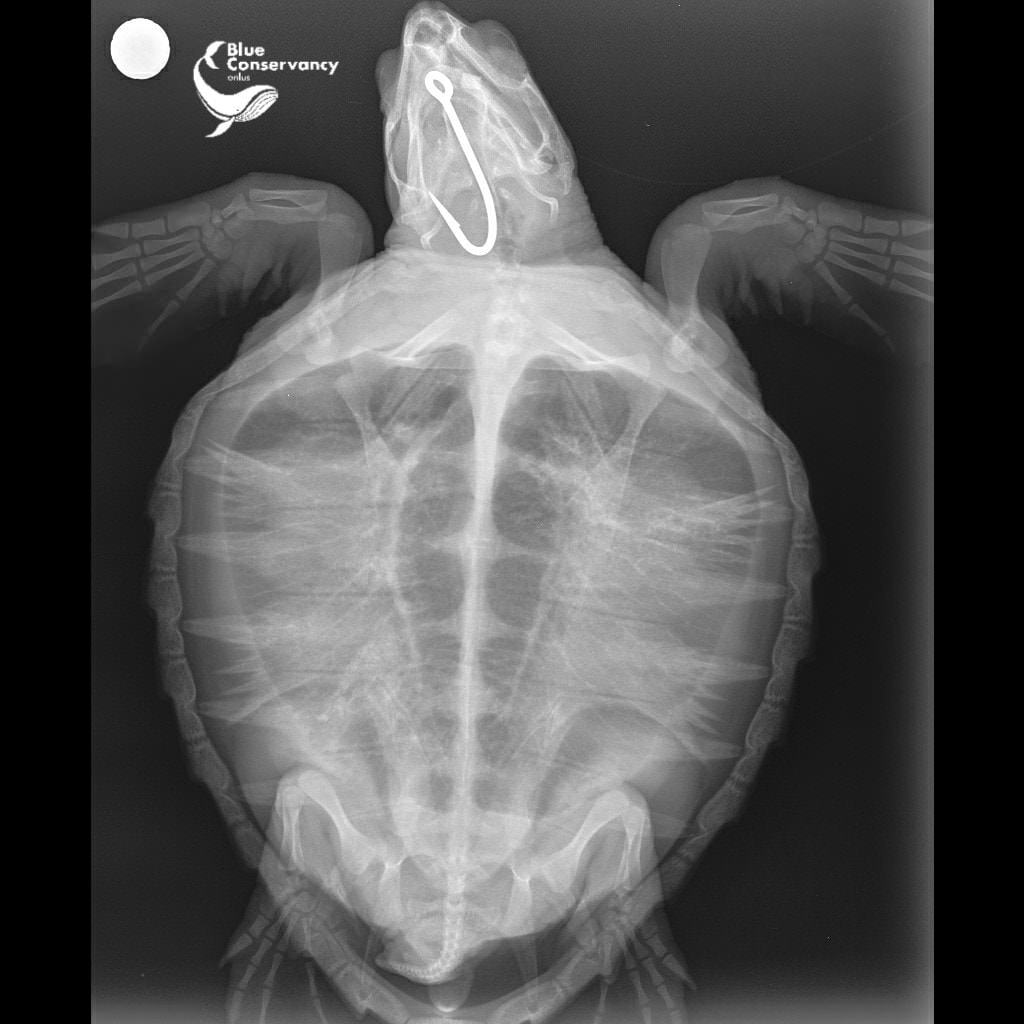

Tartaruga ferita da un amo gigantesco, soccorsa a Brancaleone

BRANCALEONE L’ultimissimo arrivo nel Centro Recupero Tartarughe Marine di Brancaleone è una piccola Caretta caretta del peso di appena 3kg (circa 2 anni di età) che ha abboccato ad un amo gigantesco (foto in basso Rx). L’amo le ha perforato lingua, palato inferiore e parte dell’esofago. Sono ami destinati alla pesca di tonno e pesce spada, in cui sono posizionate delle esche (sardine o calamari) che attirano le malcapitate creature che passano di lì. Cecilia (così l’hanno chiamata nel Crtm) sarà sottoposta a chirurgia questa stessa mattina a opera delle sapienti mani del Prof. Di Bello e del suo team (SeaTurtle Clinic MedVet Uniba).